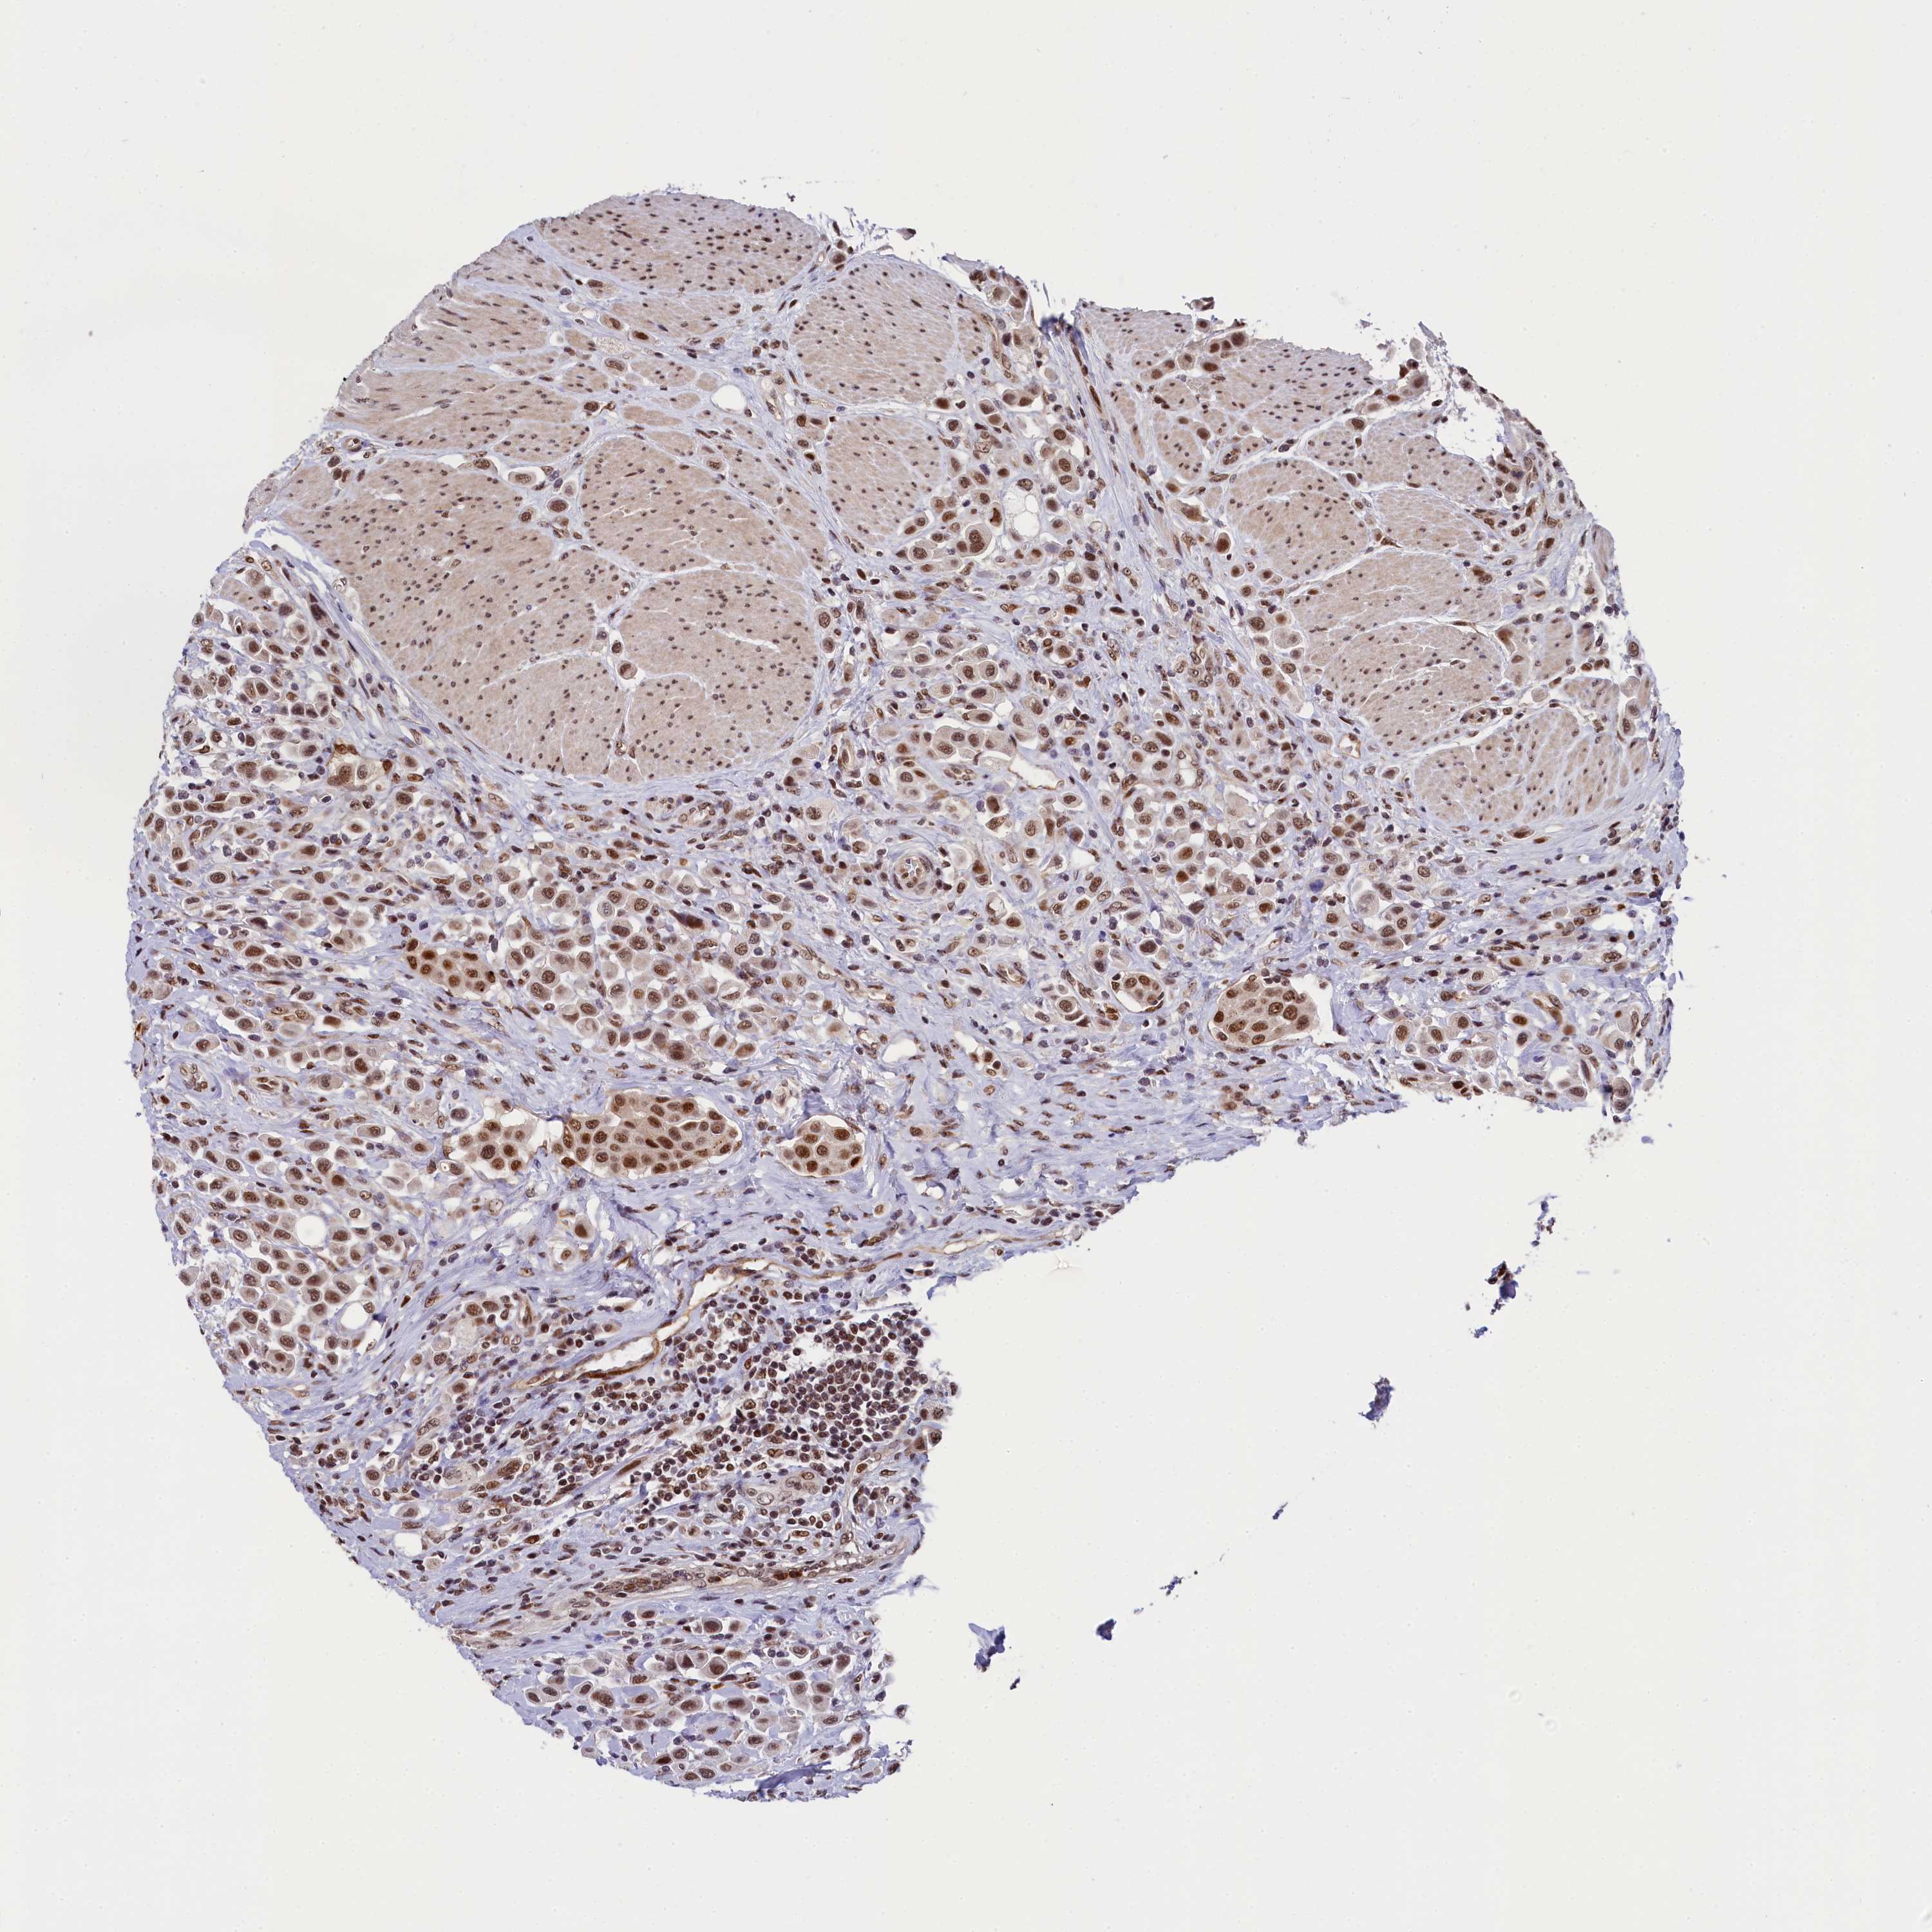

UROTHELIAL CANCER - Protein expressioni

A mouse-over function shows sample information and annotation data. Click on an image to view it in a full screen mode. Samples can be filtered based on level of antibody staining by selecting one or several of the following categories: high, medium, low and not detected. The assay and annotation is described here.

Note that samples used for immunohistochemistry by the Human Protein Atlas do not correspond to samples in the TCGA dataset.

Antibody stainingi

Antibody staining in the annotated cell types in the current human tissue is reported as not detected, low, medium, or high, based on conventional immunohistochemistry profiling in selected tissues. This score is based on the combination of the staining intensity and fraction of stained cells.

Each image is clickable and will lead to virtual microscopy that enables deeper exploration of all samples and also displays staining intensity scores, fraction scores and subcellular localization as well as patient and tissue information for each sample.

Antibody HPA041124

Staining

High

Medium

Low

Not detected

Intensity

Strong

Moderate

Weak

Negative

Quantity

>75%

75%-25%

<25%

None

Location

Nuclear

Cytoplasmic/membranous

Cytoplasmic/membranous,nuclear

Urothelial carcinoma, High grade